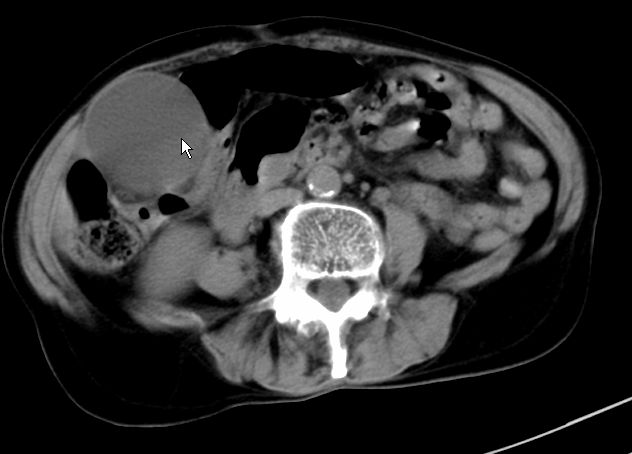

以下是引用zjzjr在2008-12-16 12:49:00的发言:[br]肝内外胆管全程扩张,胆囊明显增大,未见占位征像.建议mrcp.

以下是引用jiangjing在2008-12-16 13:19:00的发言:[br]肝内外胆管全程扩张,胆囊明显增大,扩张胆总管下段径较中上段小,未见胰管扩张,提示胆总管远端梗阻伴感染.建议增强及mrcp 检查

以下是引用朱亮在2008-12-16 12:54:00的发言:[br]胆总管远端应薄层扫描 胆总管逐渐变细 考虑胆系慢性炎症